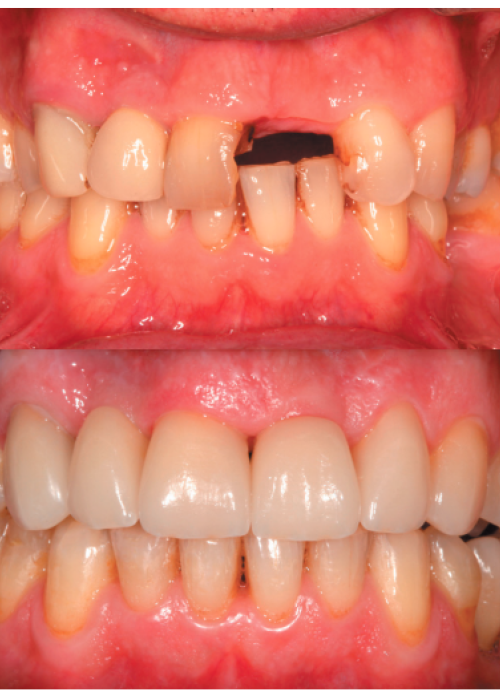

Explantación de implante mal posicionado en sector estético y regeneración posterior con injerto en bloque

Implant explantation poorly positioned in an aesthetic sector and subsequent regeneration with block grafting. Clinical case